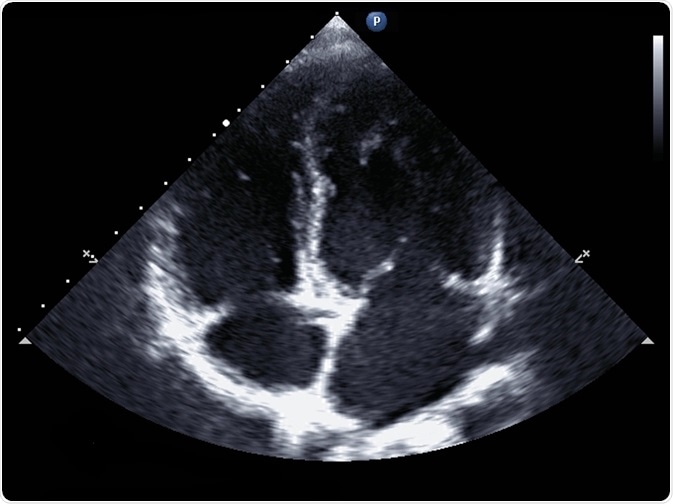

Standard transthoracic two-dimensional echocardiography in a patient with hypertension - picture by kalewa

kalewa | Shutterstock

In standard echocardiography, a black and white image is produced in real-time, allowing for an accurate assessment of chamber size and thickness.

The size of each ventricle can also be calculated to diagnose myocardial hypertrophy, a heart enlargement that more commonly affects the left ventricle and occurs in diseases such as heart failure. The 2-dimensional moving picture of the heart also allows the assessment of cardiac valve function and the identification of congenital disabilities.